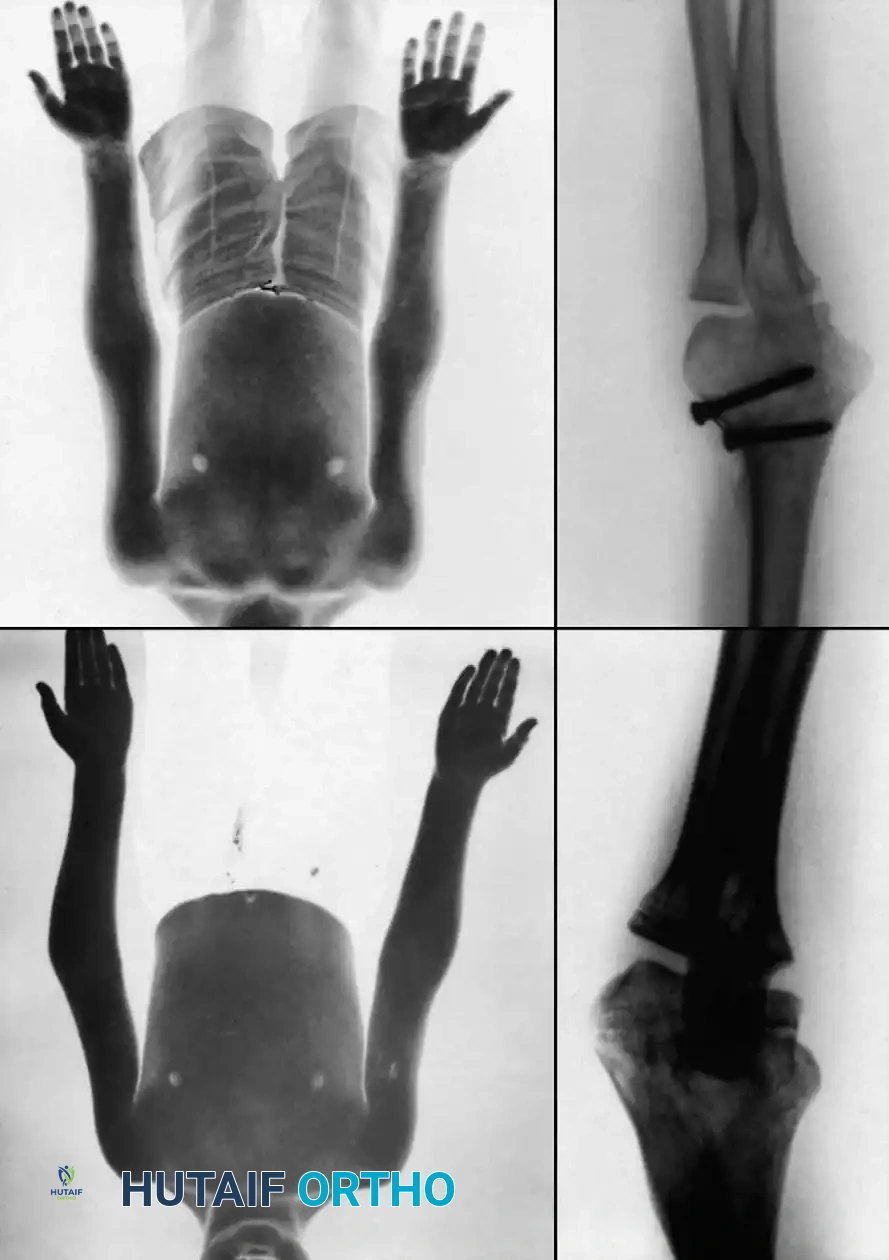

COMPREHENSIVE SURGICAL AND RADIOGRAPHIC ATLAS

The following gallery provides an exhaustive visual reference for the varied presentations, fluoroscopic interventions, and advanced reconstructive techniques associated with pediatric elbow trauma and radial neck fractures.

Preoperative Radiographic Evaluation

Intraoperative Fluoroscopy and Pin Placement